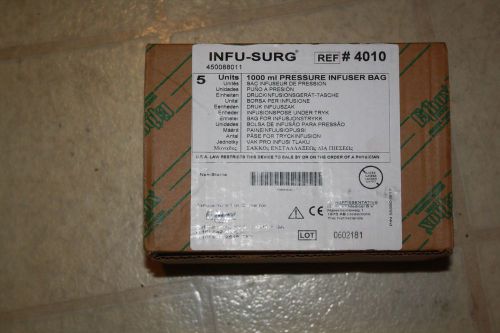

LOT OF ONE CASE (5) ETHOX Pressure Infuser Bags 1000ML